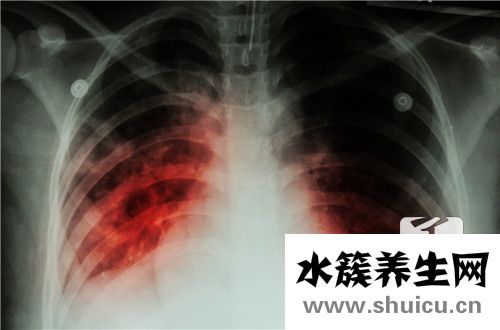

除了吸氣系統,我們還有肺的功能。因為呼吸系統失控對系統至關重要,如果肺部出現常見問題,也說明患者已經失去了自主呼吸的功能,甚至可能繼續代表疾病的發生。因此,我們應該妥善處理與肺功能有關的問題。

呼吸道病癥在肺功能檢查中的主要表現關鍵有:

1、阻塞性肺氣腫變病:指因為多種要素導致呼吸系統狹小而出現氣旋遇阻的改變,在其中以哮喘更為顯著。

2、約束性變病:指肺臟呼吸運動受限制而出現肺通氣量降低的改變,如肺氣腫、胸膜炎及液氣胸等,均有不一樣水平的肺通氣量降低。

3、混合型變病:指阻塞性肺氣腫和約束性變病二者并行不悖,如漫性阻塞性肺病及哮喘末期、塵肺、小孩支氣管肺炎等。